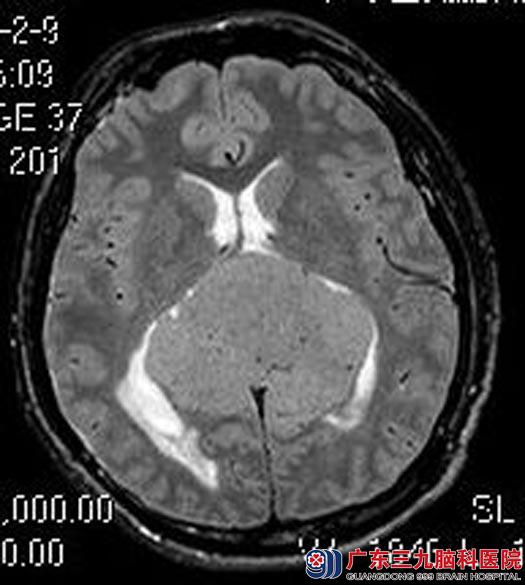

头颅MR检查提示:松果体上方正中大脑镰两旁占位性病变,大小约为7.9cm×6.5cm×6.2cm;邻近脑组织受压移位,考虑脑膜瘤可能性大。头颅CTA提示:松果体上方正中巨大软组织肿块,强化明显,其内较多迂曲血管分布,周缘较多血管缠绕,邻近双侧大脑前动脉、大脑大静脉及分支受压明显移位,邻近直窦前部及下矢状窦部分包绕。

▲头颅MR